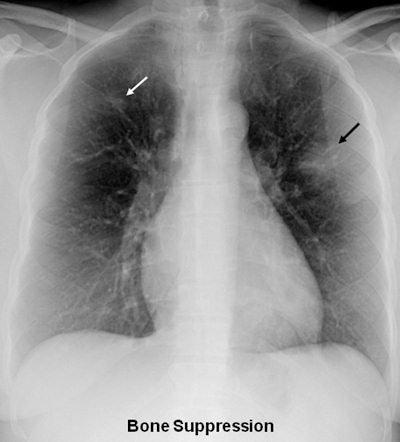

Thanks to its ability to improve the conspicuity of focal lung disease, bone suppression image processing can significantly improve radiologists' accuracy in identifying focal pneumonia on chest radiographs, according to new research published online on 5 July by European Radiology.

Bone suppression imaging software (SoftView version 2.2, Riverain Technologies) was applied to the resulting 56 chest x-rays. Eight radiologists, including six attending radiologists with a mean experience of 12 years in reading chest x-rays, and two radiology residents, were asked to provide their confidence level for the presence of a focal opacity compatible for pneumonia for each lung.

"Focal pneumonias were frequently difficult to detect on the standard [chest x-rays] but were relatively more conspicuous, and therefore easier to detect on the [bone-suppression imaging] images," the authors wrote.